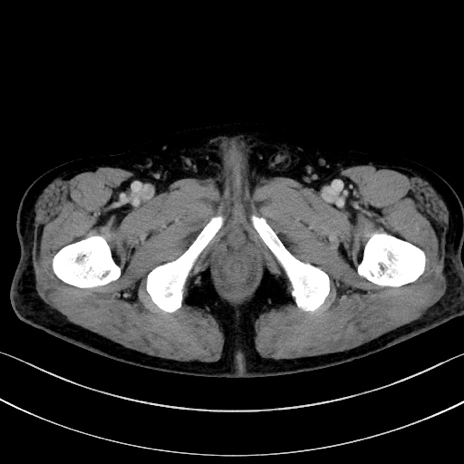

症例15(横断像)

【症例】70歳代男性

【主訴】腹痛

【現病歴】今朝から腹痛あり。全体的に痛い。特に左上の方。排ガスが今日はない。冷や汗が出る。

【既往歴】直腸癌術後

【身体所見】左側腹部〜上腹部に圧痛あり。腹膜刺激症状明らかなではない。軽度反跳痛。左下腹部に術後瘢痕あり。

【データ】WBC 7700、CRP 0.02